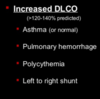

- What does the image describe? The answer choices are below.

- Locus Heterogeneity

- Mosaicism

- Pleiotropy

- Penetrance - Incomplete

- Penetrance - Age-dependent

- Variable expression

- New mutations (de novo)

Pleiotropy

Identify factors that may affect the disease expressing genes and explain their contribution to human diseases utilizing specific examples.

- What does the image describe? The answer choices are below.

- Locus Heterogeneity

- Mosaicism

- Pleiotropy

- Penetrance - Incomplete

- Penetrance - Age-dependent

- Variable expression

- New mutations (de novo)

New mutations (de novo)

Identify factors that may affect the disease expressing genes and explain their contribution to human diseases utilizing specific examples.

- What does the image describe? The answer choices are below.

- Locus Heterogeneity

- Mosaicism

- Pleiotropy

- Penetrance - Incomplete

- Penetrance - Age-dependent

- Variable expression

- New mutations (de novo)

Mosaicism (germline)

Identify factors that may affect the disease expressing genes and explain their contribution to human diseases utilizing specific examples.

- What does the image describe? The answer choices are below.

- Locus Heterogeneity

- Mosaicism

- Pleiotropy

- Penetrance - Incomplete

- Penetrance - Age-dependent

- Variable expression

- New mutations (de novo)

Penetrance - Incomplete

Identify factors that may affect the disease expressing genes and explain their contribution to human diseases utilizing specific examples.

- What does the image describe? The answer choices are below.

- Locus Heterogeneity

- Mosaicism

- Pleiotropy

- Penetrance - Incomplete

- Penetrance - Age-dependent

- Variable expression

- New mutations (de novo)

Penetrance - Age-dependent

Identify factors that may affect the disease expressing genes and explain their contribution to human diseases utilizing specific examples.

- What does the image describe? The answer choices are below.

- Locus Heterogeneity

- Mosaicism

- Pleiotropy

- Penetrance - Incomplete

- Penetrance - Age-dependent

- Variable expression

- New mutations (de novo)

Locus Heterogeneity

Identify factors that may affect the disease expressing genes and explain their contribution to human diseases utilizing specific examples.

- What does the image describe? The answer choices are below.

- Locus Heterogeneity

- Mosaicism

- Pleiotropy

- Penetrance - Incomplete

- Penetrance - Age-dependent

- Variable expression

- New mutations (de novo)

Variable expression